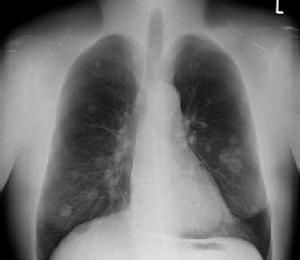

(三)X線檢查

支氣管肺炎的病因不同,因此在X線上所表現的變化既有共同點,又各有其特點。早期見肺紋理增粗,以後出現小斑片狀陰影,以雙肺下野、中內帶及心膈區居多,並可伴有肺不張或肺氣腫,斑片狀陰影亦可融合成大片,甚至波及整個節段。

1.病灶的形態

支氣管肺炎主要是肺泡內有炎性滲出,多沿支氣管蔓延而侵犯小葉、肺段或大葉。X線徵象可表現為非特異性小斑片狀肺實質浸潤陰影,以兩肺、心膈角區及中內帶較多,這種變化常見於2歲以下的嬰幼兒,小斑片病灶可部分融合在一起成為大片狀浸潤影,甚至可類似節段或大葉肺炎的形態。若病變中出現較多的小圓形病灶時,就應考慮可能有多種混合的化膿性感染存在。

2.肺不張和肺氣腫征

由於支氣管內分泌物和肺炎的滲出物阻塞,可產生部分性肺不張或肺氣腫,在小兒肺炎中肺氣腫是早期常見徵象之一,中毒症狀越重肺氣腫就越明顯,在病程中出現泡性肺氣腫及縱隔氣腫的機會也比成人多見。

3.肺間質X線征

嬰兒的肺間質組織發育好,患支氣管肺炎時,可以出現一些肺間質的X線徵象,常見兩肺中內帶紋理增多、模糊。流感病毒肺炎、麻疹病毒肺炎、百日咳桿菌肺炎所引起的肺間質炎性反應都可有這些X線徵象。

4.肺門X線征

肺門周圍局部的淋巴結大多數不腫大或僅呈現肺門陰影增深,甚至肺門周圍濕潤。

5.胸膜的X線征

胸膜改變較少,有時可出現一側或雙側胸膜炎或胸腔積液的現象。儘管各種不同病因的支氣管肺炎在X線表現上有共同點,但又不盡相同,因此,必須掌握好各種肺炎的X線表現,密切結合臨床症狀才能做出正確診斷。